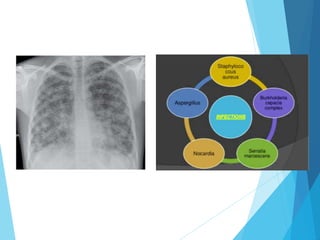

CHRONIC GRANULOMATOUS

DISEASE

• Defect in genes encoding

components of phagocyte

oxidase

• 2 variants:

1) X linked: Defect in

membrane bound

component i.e. gp91phox

2) Autosomal recessive :

Defect in cytoplasmic

component i.e. P47phox,

p67phox